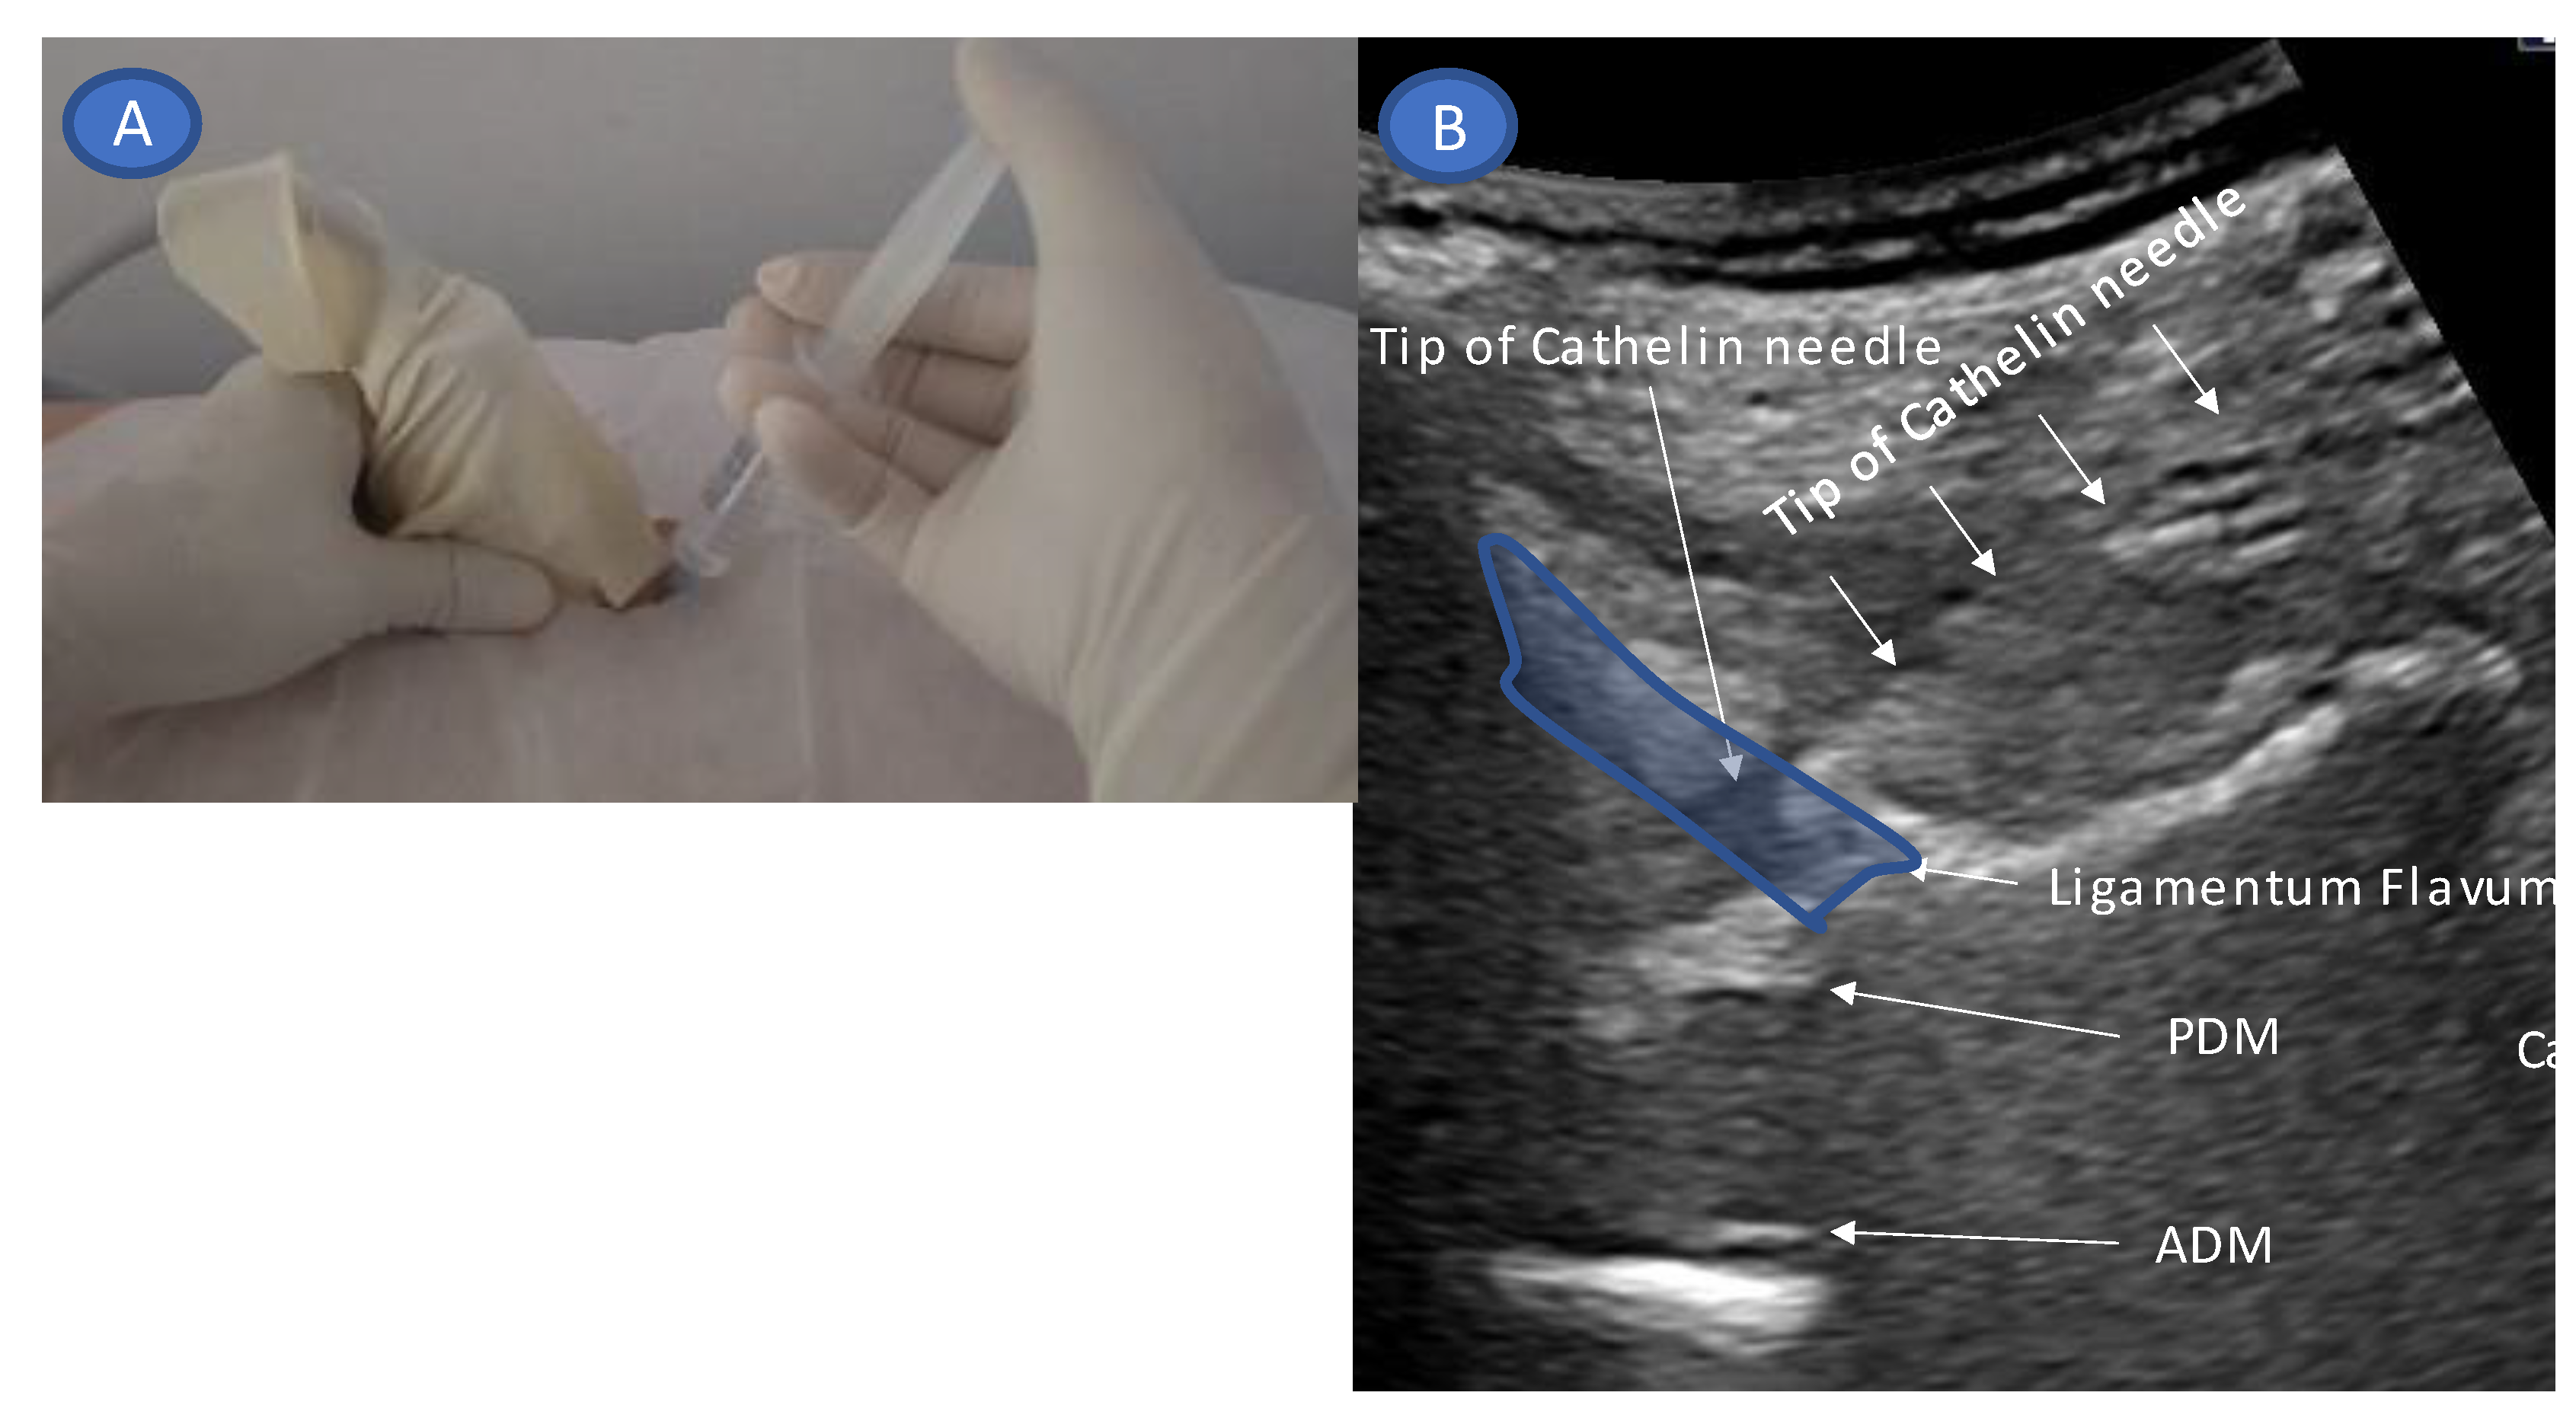

- Accurate needle tip guidance into the ligamentum flavum behind the epidural fat layer;

- Palpation of resistance by finger sense during ligamentum flavum insertion while confirming with sonography;

- Confirmation of the position of the needle tip in the ligamentum flavum;

- Tracing the spread of the drug in the epidural space using SMI during the injection.